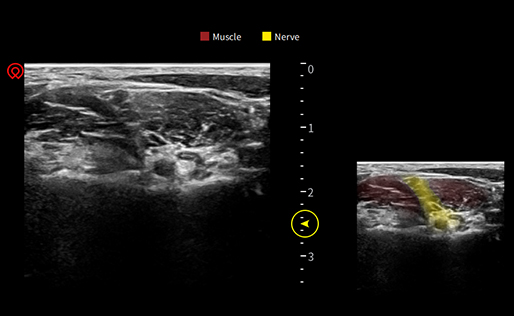

wiNerve

Intelligente AI-Nervenerkennung

Erkennung in Echtzeit

Cloud-L?sung

Unterstützung mehrerer Nerven